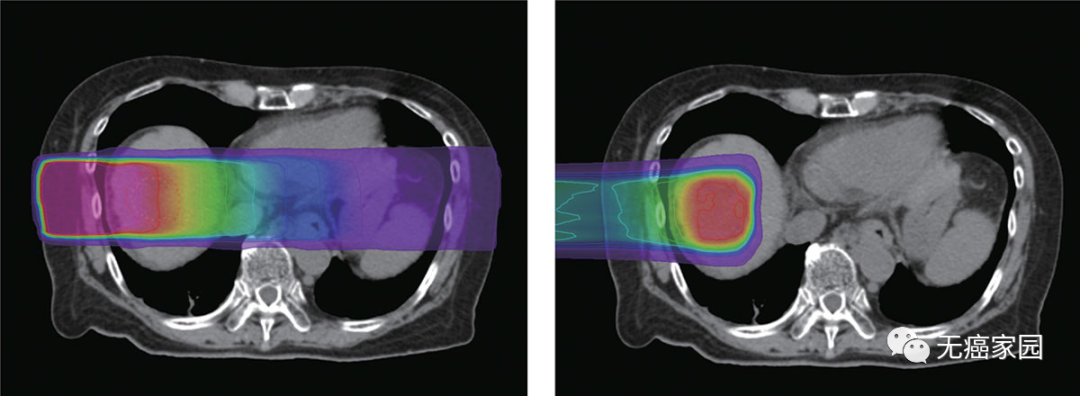

长期以来,人们都知道传统放疗使用的X射线(也称为光子)疗法会导致各种副作用,比如食管癌的放疗会造成不同程度的吞咽不适,脑瘤的放疗会导致精神不振等症状,但实际上接受...